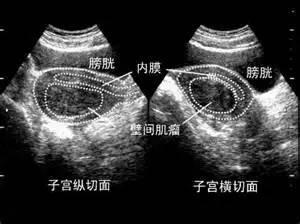

超声波检查显示19×12×9cm的羊膜囊(7.5×4.7×3.5英尺)的一部分通过子宫左壁的一个洞下滑了,胎儿的腿也处于膝盖稍微偏上的位置。MRI扫描显示子宫壁的裂隙扩大到了2.5cm(1英尺)(图中箭头所示)。